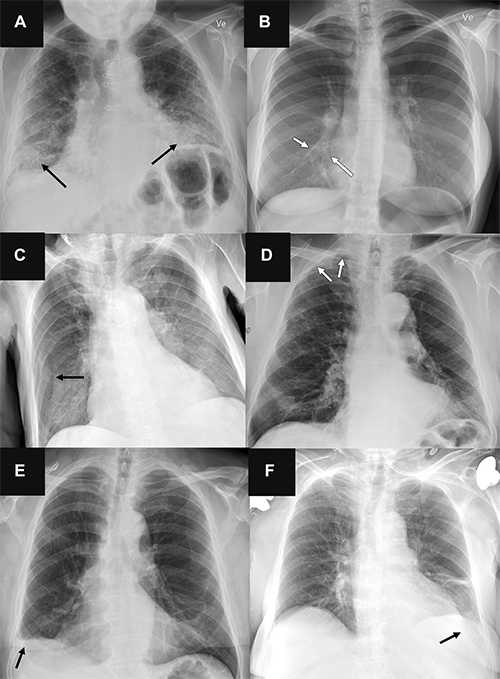

Plesner Radiology Fig 6 AI Chest X-ray

Representative chest radiographs in six patients show (A, C, E) false-positive findings and (B, D, F) false-negative findings as identified by the artificial intelligence (AI) tools. These examples were all correctly classified by the clinical radiology reports. (A) Posteroanterior chest radiograph in a 71-year-old male patient who underwent examination due to progression of dyspnea shows bilateral fibrosis (arrows), which was misclassified as airspace disease by all four AI tools. (B) Posteroanterior chest radiograph in a 31-year-old female patient referred for radiography due to month-long coughing shows subtle airspace opacity at the right cardiac border (arrows), which was missed by all AI tools. (C) Anteroposterior chest radiograph in a 78-year-old male patient referred after placement of a central venous catheter shows a skin fold on the right side (arrow), which was misclassified as pneumothorax by all AI tools. (D) Posteroanterior chest radiograph in a 78-year-old male patient referred to rule out pneumothorax shows very subtle apical right-sided pneumothorax (arrows), which was missed by all AI tools except for vendor B (with the high sensitivity threshold). (E) Posteroanterior chest radiograph in a 72-year-old male patient referred for radiography without a specified reason shows chronic rounding of the costophrenic angle (arrow), which was mistaken for pleural effusion by all AI tools and verified according to the reference standard in a corresponding chest CT image. (F) Anteroposterior chest radiograph in a 76-year-old female patient referred for radiography due to suspicion of congestion and/or pneumonia shows a very subtle left-sided pleural effusion (arrow), which was missed by all three AI tools that were capable of analyzing anteroposterior chest radiographs for pleural effusion.